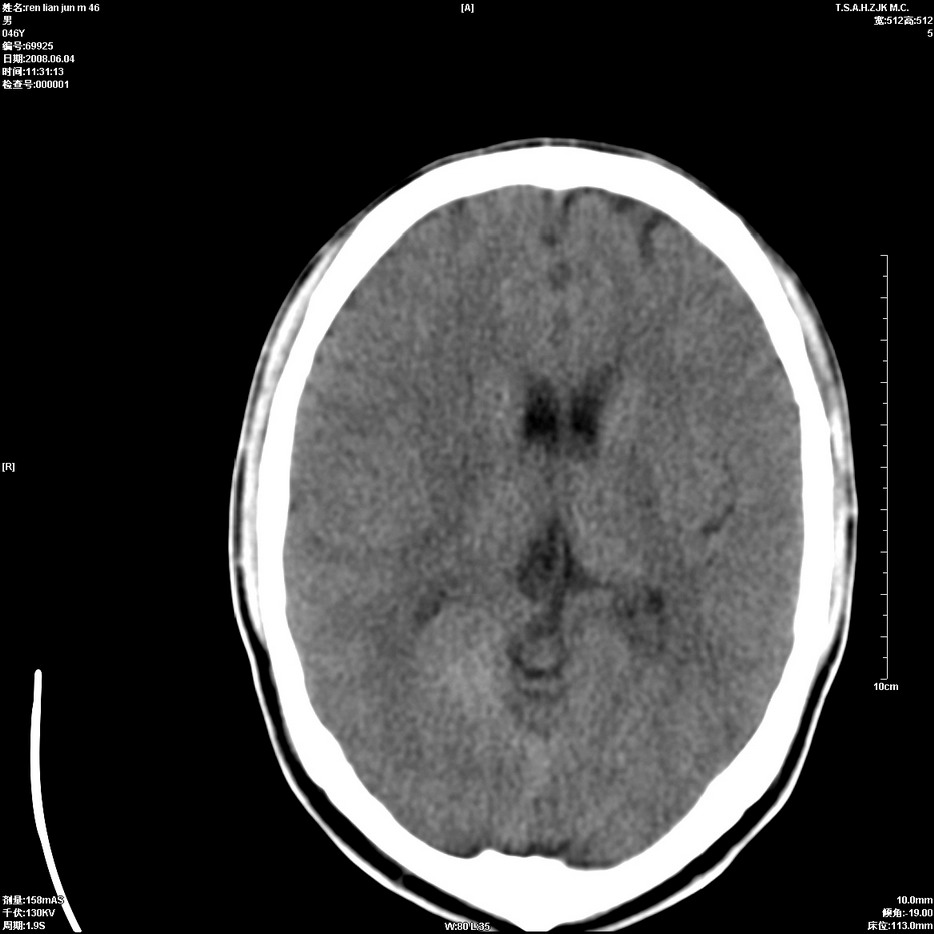

以下是引用qiu999在2008-6-5 17:14:00的发言:[br]考虑右肺中心型肺癌.颅内应做增强检查.

以下是引用形影不离在2008-6-5 19:18:00的发言:[br]右肺中心型肺癌并纵隔及左侧腋窝淋巴结转移,颅内应做增强检查。

以下是引用杀毒软件在2008-6-5 18:33:00的发言:[br]支持考虑右肺中心型肺癌,颅内病变是不是转移,不好说